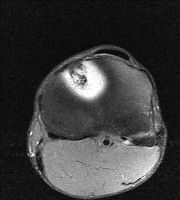

무릎 mri 간단히 봐주실 수 있으시나요 ㅠㅠ

안녕하세요 8년전 십자인대 수술하고 최근 무리한 운동에 무릎 불편감이 생겨서

mri 찍었습니다.

진단결과는 첫 찍은 병원에서 활액막염 이라는 진단을 받았습니다. 혹시 봐주실 수 있으실까요?

올라온 MRI가 단편적이라서 정확한 진단에 어려움이 있지만 십자인대에는 큰 이상이 있지는 않은것 같으며, 무릎관절내 물이 있는 것으로 보아 활액막염의 진단이 맞을 것 같습니다.

하지만 단편적인 영상이기 때문에 촬영병원에서 정확한 판독지 등을 받으시는 것이 좋겠습니다.